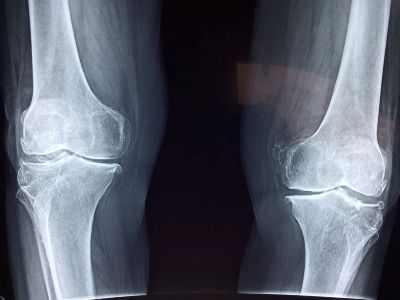

L'XLH è causata da una mutazione del gene PHEX che provoca livelli eccessivi del fattore di crescita dei fibroblasti 23 (FGF23), e questo, a sua volta, è causa della perdita di fosfato per via renale. I bassi livelli di fosfato nel sangue hanno conseguenze negative sulla mineralizzazione di ossa e denti, sulle articolazioni e sulla muscolatura. I problemi clinici iniziano nell'infanzia (deformità agli arti inferiori, rachitismo, rallentamento della crescita) continuano durante l’età evolutiva e persistono o peggiorano nell'età adulta (fratture, dolore articolare e debolezza muscolare). L’incidenza della patologia – si legge sul sito dell’Associazione Italiana Sostegno Malattie Metaboliche Ereditarie (AISMME) - è di circa 1 su 21-25.000 nati vivi.